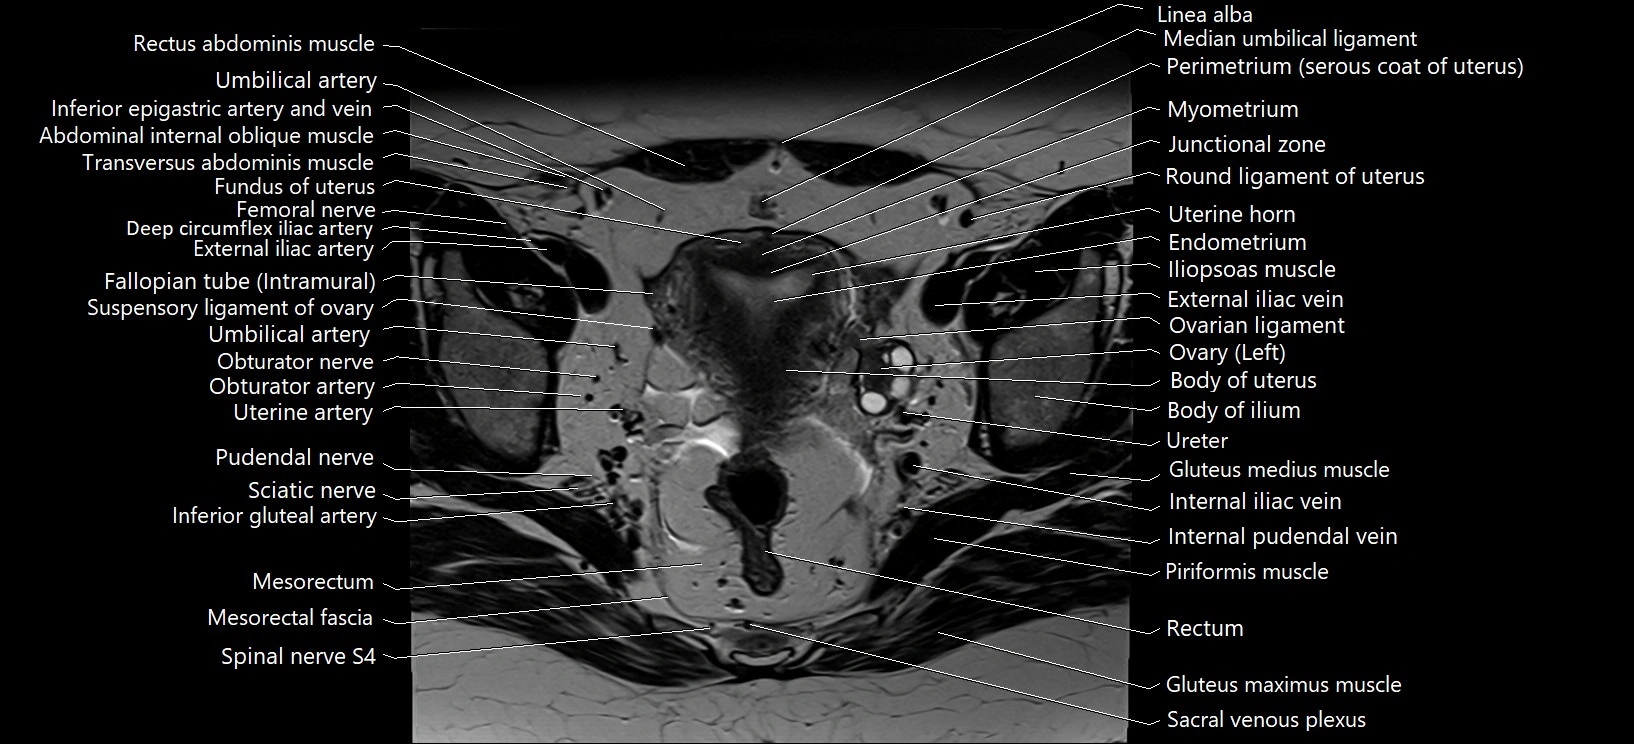

- Body of uterus

- Endometrium of uterus

- Fallopian tube

- Fundus of uterus

- Iliopsoas muscle

- Iliopsoas tendon

- Inferior mesenteric vein

- Internal iliac vein

- Internal pudendal vein

- Junctional zone of uterus

- Median umbilical ligament

- Mesorectal fascia

- Mesorectum

- Myometrium of uterus

- Perimetrium of uterus

- Piriformis muscle

- Pudendal nerve

- Rectum

- Round ligament of uterus

- Sacroiliac joint

- Sigmoid colon

- Spinal nerve S1

- Spinal nerve S2

- Spinal nerve S3

- Spinal nerve S4

- Superior rectal artery

- Suspensory ligament of ovary

- Umbilical artery

- Ureters

- Uterine artery

- Uterine horn